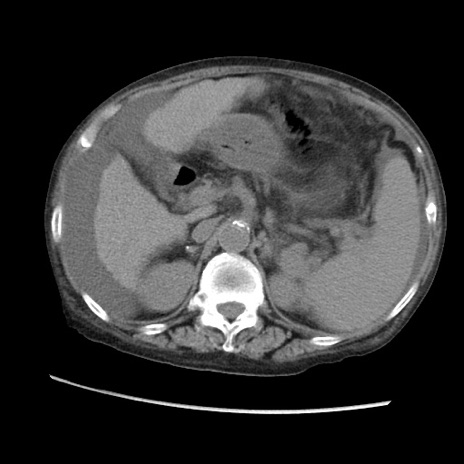

症例31(横断像)

【症例】80歳代 女性

【主訴】腹部膨満感

【現病歴】他院にて肝硬変にてフォロー中。1週間前から便秘、腹部膨満感、臍部腫瘤あり受診となる。

【既往歴】肝硬変

【身体所見】腹部膨隆あり、皮膚変化なし、疼痛なし。

【データ】WBC 4600、CRP 0.25